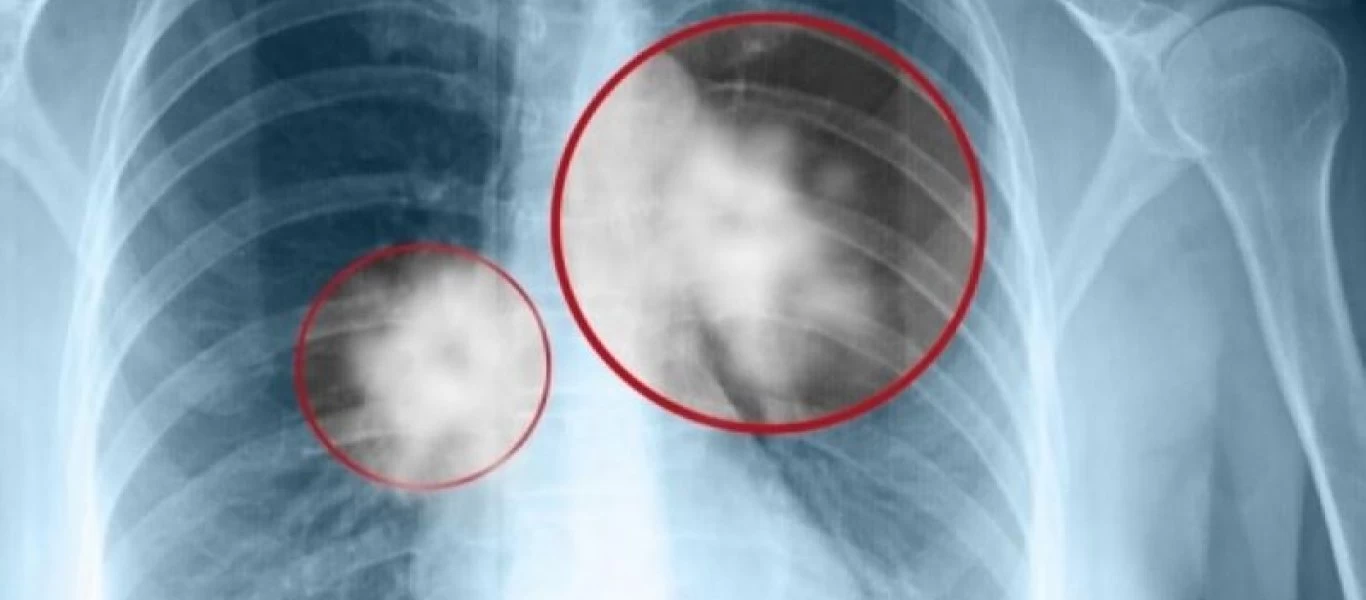

Τα πρώιμα σημάδια του καρκίνου του πνεύμονα που πρέπει να ξέρεις

Όταν πρόκειται για την υγεία μας, ένας από τους καλύτερους τρόπους για να προστατεύσουμε τον εαυτό μας είναι να μην παραλείπουμε τις ιατρικές μας εξετάσεις αλλά και να μην αγνοούμε τα σημάδια που μας ...